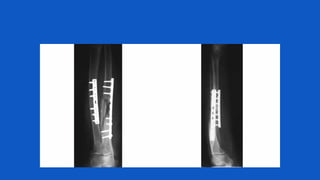

Indications for Internal Fixation in Open

Fractures

1)Periarticular fractures

– Distal/proximal tibia

– Distal/proximal

femur

humerus

– Proximal ulnar radius

– Selected distal

radius/ulna

– Acetabulum/pelvis

2) Diaphyseal fractures

– Femur

– Tibia

– Humerus

– Radius/ulna

Plates

• Open diaphyseal fractures of the radius andulna as

well asthe humerus are best managedwith plate

fixation.

• The plate fixation of lower extremity diaphyseal

fractures is generally not recommended due to

higher rate of infections.

INTRAMEDULLARY NAILING

• Locked intramedullary nailing has been established as

the treatment of choice for most diaphyseal fractures

in lower extremity.

• Intramedullary nails can be inserted with no further

disruption of the already injured soft-tissue envelope

and preserves the remaining extra osseous blood

supply to corticalbone.